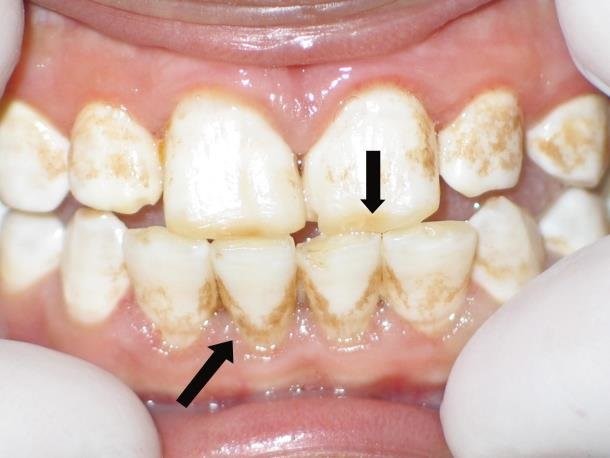

بسته به شدت، این نقص میتواند مانند یک تورفتگی کوچک در دندان به نظر برسد یا چند دندان را در سراسر دهان تحت تاثیر قرار دهد. ممکن است تغییر رنگ دندان موضعی باشد، یا تمام دندان میتواند به رنگ قهوهای تیره درآید. این امر میتواند دهان و دندان را فوقالعاده حساس کند، به خصوص برای کودکانی نوپا که تازه یاد گرفتهاند که چگونه احساسات خود را بیان کنند.

هیپوپلازی مینای دندان میتواند به دو روش بر روی دندانها تأثیر بگذارد. این نقص گاهی به عنوان یک ساختار از دست رفته فیزیکی دندان شناخته میشود و میتواند به صورت حفره ها، شیارها یا فقط قسمتهایی از دست رفته در تاج دندان باشد. اما در روش دوم، این موضوع سبب کمبود محض ماده معدنی مینای دندان است. اگر این امر به اندازه کافی شدید باشد به دندان فرد، ظاهری شفاف خواهد داد، و اگر خفیف باشد رنگ دندان حفظ میشود.

علائم قابل مشاهده این عارضه شامل لکههای سفید، حفرهها و شیارهای سطح خارجی دندانها است.

- لکههای سفید

- لکههای زرد مایل به قهوهای (جایی که لایه زیرین عاج دیده میشود)